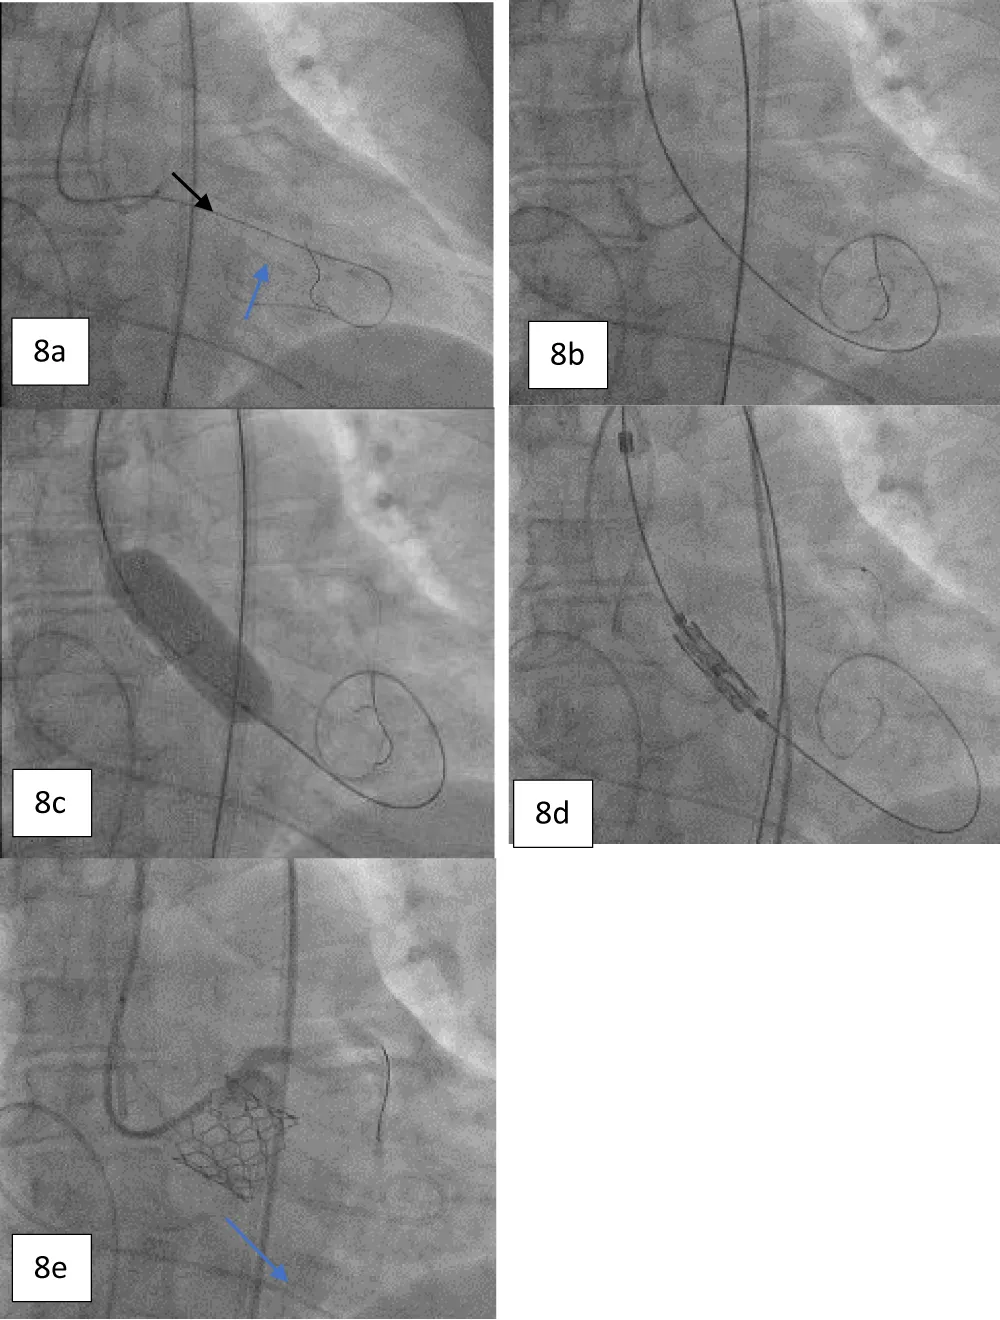

A 63-year-old female with morbid obesity (weight: 115 kg) presented with recurrent episodes of heart failure. On examination, an aortic systolic ejection murmur was audible, while the echocardiogram showed findings of severe AS with a mean gradient of 40 mmHg (Figure 6). Further, her coronary angiogram revealed non-obstructive CAD lesions in the right coronary and LAD arteries. The heart failure episodes were attributed due to severe AS; therefore, valve replacement was planned. The decision of the Heart Team was in favor of TAVI in view of the patient’s advanced age and morbid obesity. Hence, the anatomical eligibility for TAVI was assessed by contrast-enabled 3D computed tomography (CT) of the aortic root and the AV. The CT analysis revealed the bicuspid type 1a AV in the patient with fused right and left cusps. The average aortic annulus diameter was 22.1 mm, the annular area was 370.7 mm2, and the annulus perimeter was 69.2 mm (Figure 7a). The SOV diameters of the left, right, and non-coronary cusps are 28.5 mm, 26.1 mm, and 29.3 mm, respectively (Figure 7b). The heights of the RCO and LCO were 14.6 mm and 7.2 mm (Figure 7c,7d), respectively. The height of the SOV was 7.1 mm while the mean STJ height was 26.7 mm (Figure 7e). According to the iliofemoral analysis, the average diameter of the right common femoral artery (CFA) was 5.4 mm and that of the left CFA was 5.2 mm; the average diameter of the right external iliac artery (EIA) was 5.8 mm and that of the left EIA was 6.0 mm (Figure 7f).

Download Image

Figure 7: a. Contrast-enhanced 2D-CT image showing the dimensions of the aortic valve annulus (mean annulus diameter: 22.1 mm and annulus perimeter: 69.2 mm), and b. showing the SOV diameters of the left, right, and non-coronary cusps. c. Height of the LCA (7.2 mm) shown with blue arrows, and d. Height of RCA (14.6 mm) shown with arrows. e. Height of the SOV 7.1 mm, shown with yellow arrows, and f. The diameters of the iliofemoral vessels at the access site.